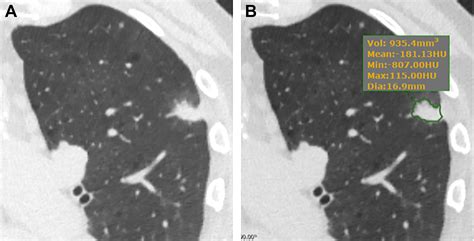

• CT Scan: Computed tomography (CT) scans provide more detailed images and are crucial for evaluating the size, shape, and density of lung nodules.

When evaluating pictures of lung nodules, radiologists look for specific characteristics that can indicate the nature of the nodule. These characteristics include:

• Size: Larger nodules are more likely to be malignant.

• Shape: Irregular or spiculated edges are often associated with cancer.

• Density: Solid nodules are more concerning than ground-glass nodules.

• Growth Rate: Rapidly growing nodules are more likely to be malignant.

Interpreting pictures of lung nodules requires expertise in radiology and an understanding of the various imaging techniques. Radiologists use specific criteria to assess the likelihood of malignancy. The Fleischner Society guidelines provide a framework for managing incidental pulmonary nodules detected on CT scans. These guidelines consider the size of the nodule and the presence of risk factors for lung cancer.

For example, a solid nodule less than 6 mm in diameter with no risk factors for lung cancer may require only follow-up imaging after 12 months. In contrast, a solid nodule greater than 8 mm in diameter with risk factors may warrant more immediate intervention, such as a biopsy or surgical resection.